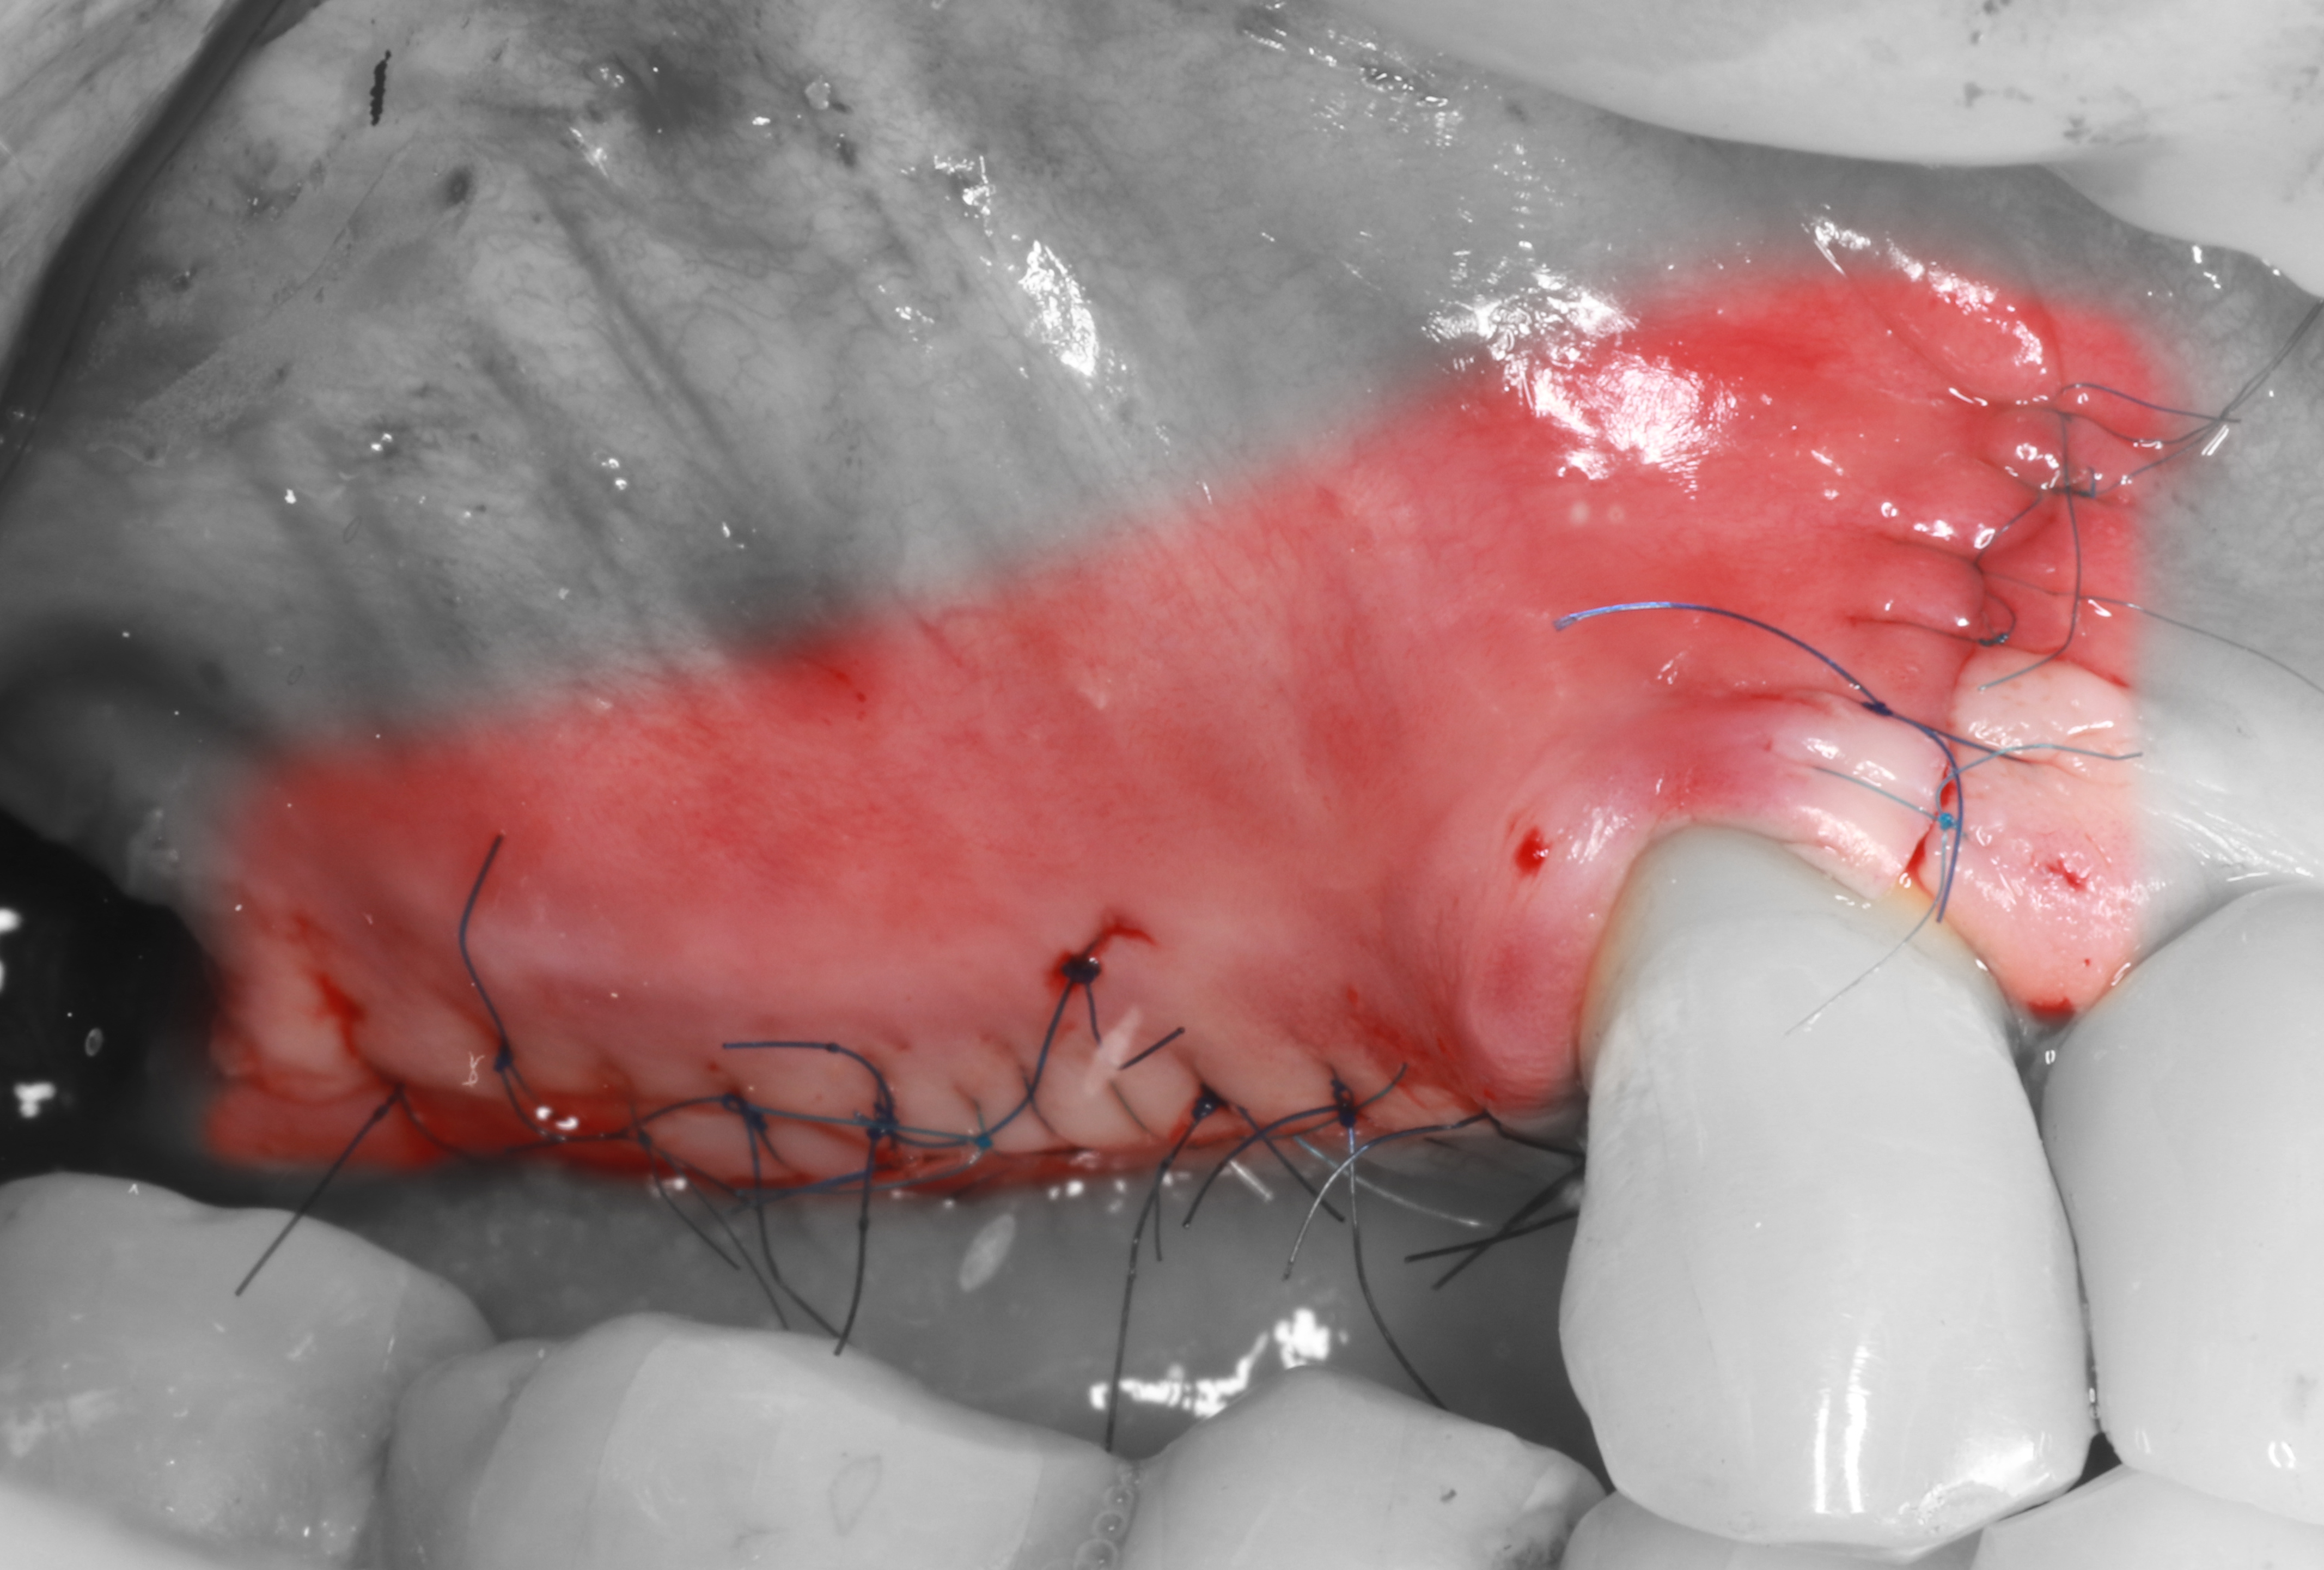

9) Рана ушита с помощью полипропилена 7/0 и резопрена 6/0.